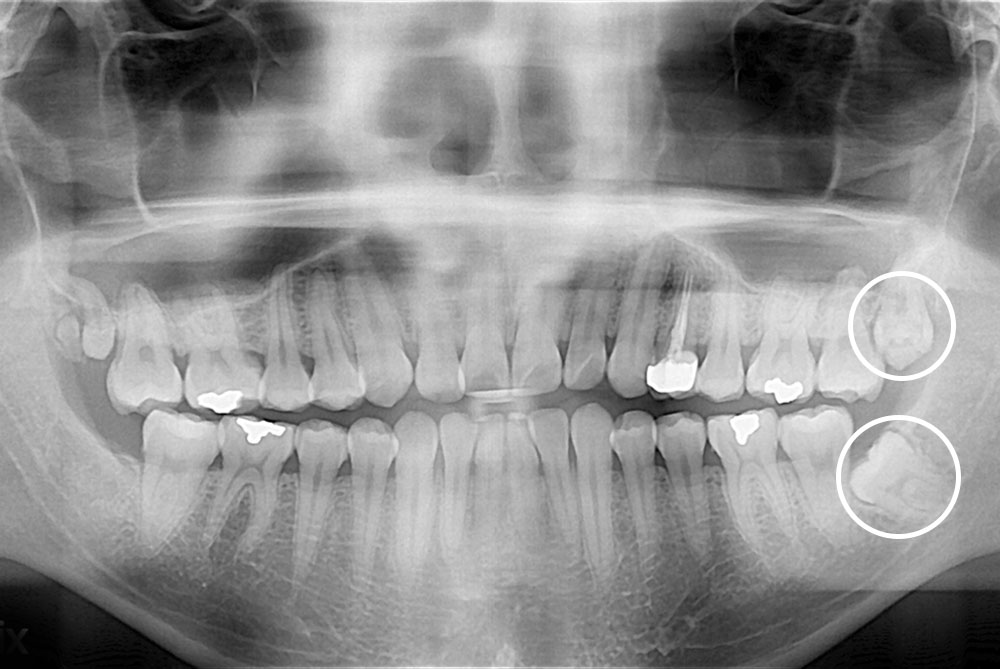

[사랑니] 매복 사랑니 발치

치료전 : 2018-11-15